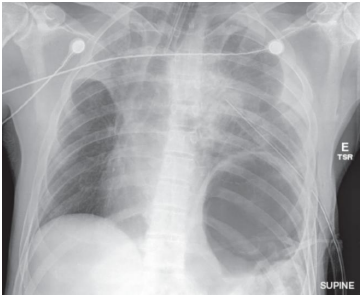

Paciente masculino, 35 anos, vítima de

politraumatismo após acidente automobilístico, é

admitido no pronto-socorro. Ao exame inicial,

apresenta-se intubado e com dreno torácico

inserido no hemitórax esquerdo devido a

suspeita de pneumotórax. Os sinais vitais

incluem pressão arterial de 90/60 mmHg,

frequência cardíaca de 120 bpm, frequência

respiratória de 30 irpm e saturação de oxigênio

de 88% em ventilação mecânica. Foi realizada a

seguinte radiografia de tórax:

Fonte: Sabiston Tratado de Cirurgia / Courtney M.

Townsend et al. 20° edição - Rio de Janeiro:

Elsevier, 2019.

Com base no caso clínico acima e nos achados da imagem, o diagnóstico mais provável é: